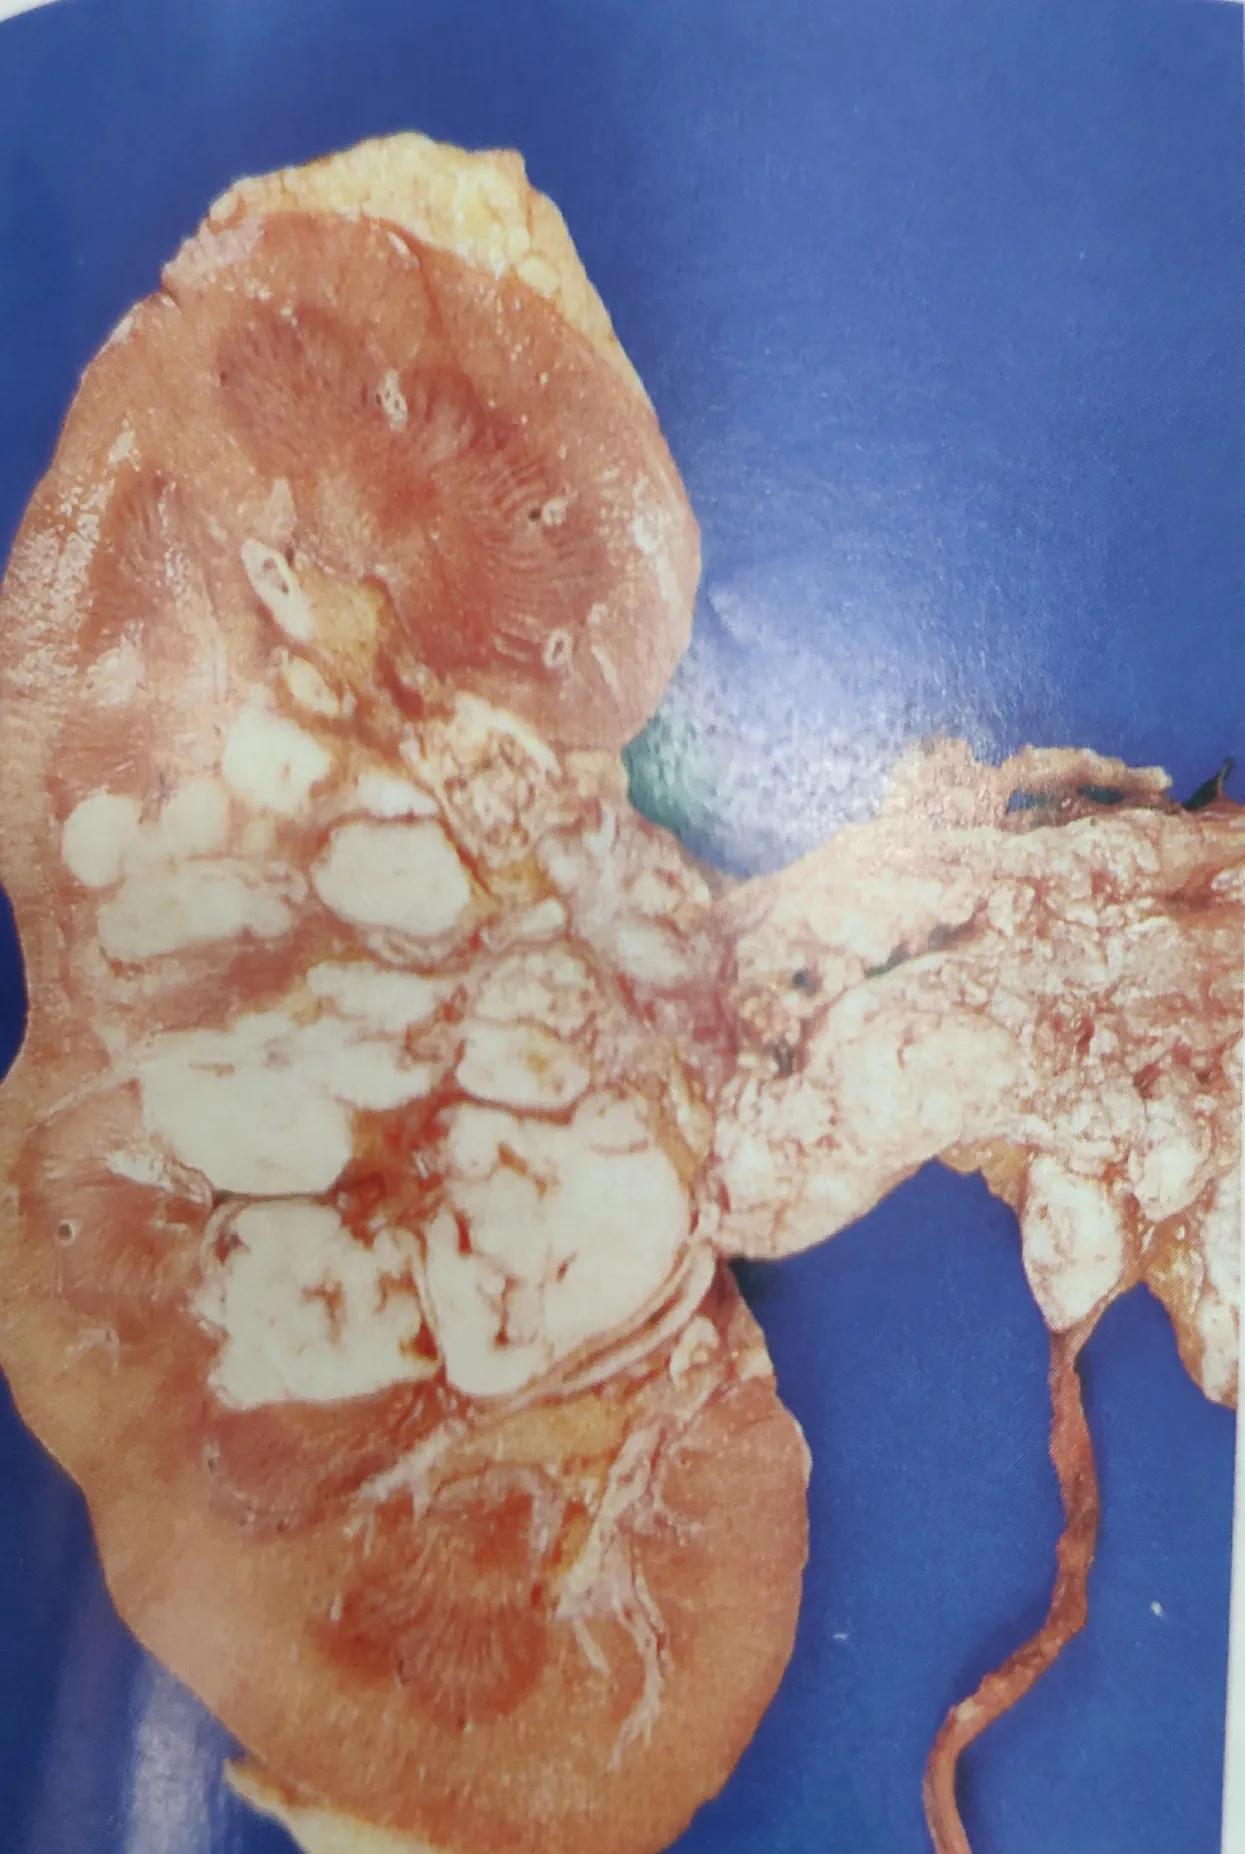

一.发生于肾实质者,主要有起源各段肾小管的肾细胞癌和肾腺瘤,以前者常见,体积多较大,伴有坏死,肿瘤切面往往呈白色均质状,更多情况下会继发坏死,出血呈多彩状,或者呈囊性。

肾透明细胞癌

肾细胞癌,多彩状

囊状肾细胞癌